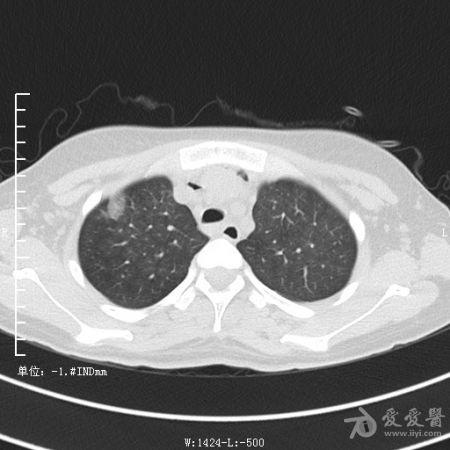

典型支气管扩张及肺水肿CT片

典型支气管扩张肺水肿